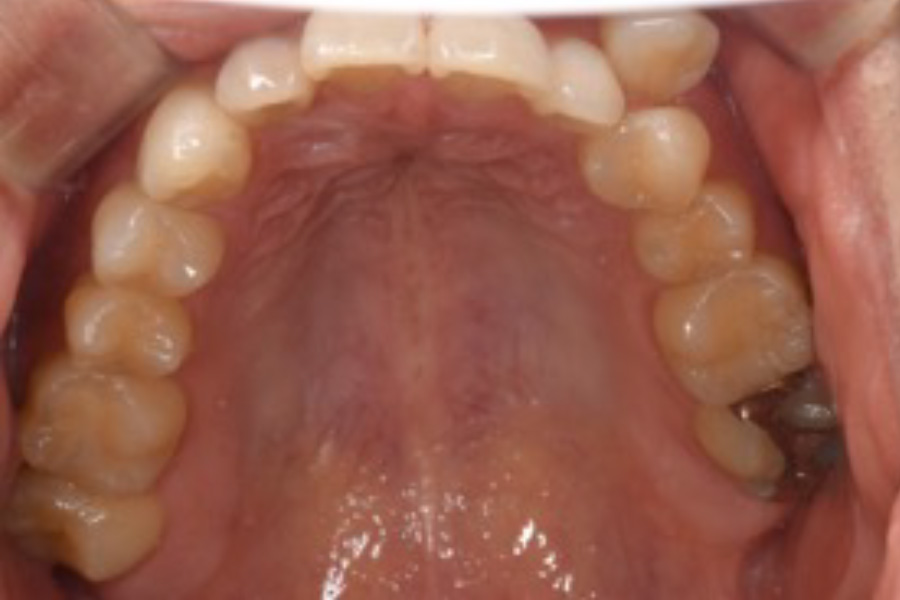

治療前

治療後

主訴 八重歯を含めた全体的なガタつき

治療内容 目立ちにくいマウスピース矯正(非抜歯矯正)

歯と歯の間に隙間をつくることにより、歯列弓を広げながら治療を行いました。